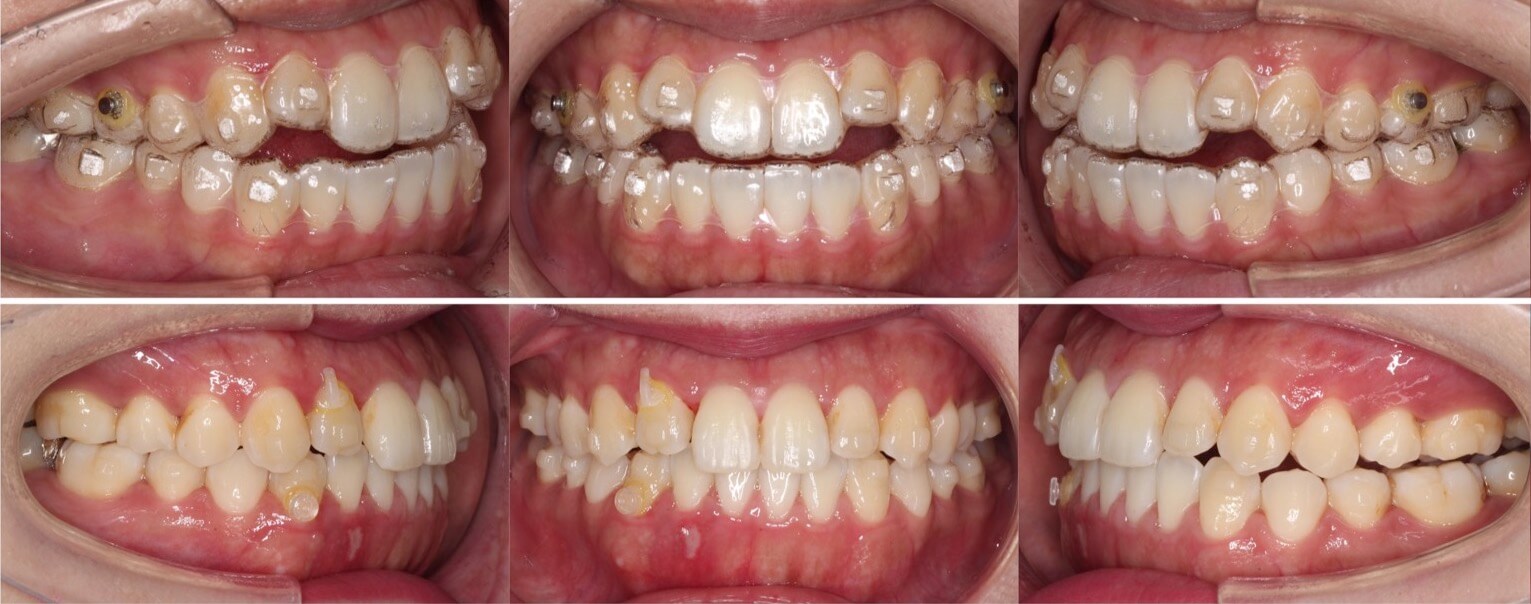

20代男性・唇側矯正装置・上下抜歯

前歯は完全に反対咬合になってはいないのですが、下あごが大きく切端咬合になっているケースです。片側に八重歯があり正中線がずれています。抜歯空隙をうまく利用して改善しました。

<症例概要> 難易度 ★★★★☆

主訴:下の前歯の突出

年齢・性別:20代男性

住まい:千葉県香取郡

症状:切端咬合・重度叢生・正中線不一致

治療方針:上下小臼歯抜歯・空隙閉鎖

治療装置:唇側矯正装置

固定装置:上バイヘリックス装置・III級顎間ゴム

抜歯:上第二小臼歯・下第一小臼歯(計4本)

治療期間:2年5か月

リテーナー:上下フィックスタイプ+プレートタイプ

治療費用:968,000(税込)

代表的副作用:痛み・治療後の後戻り・歯根吸収・歯髄壊死・歯肉退縮